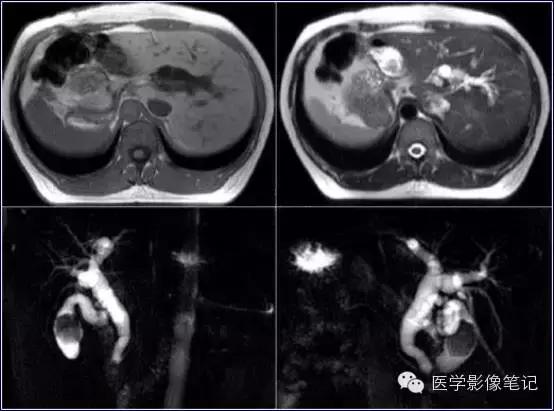

獭尾肝/包围肝

利德尔叶(Riedel’s Lobe)

肝的右下部向下如舌状突出生长的舌叶。

乳头状突

肝尾状叶结构,常误认为肿大淋巴结。